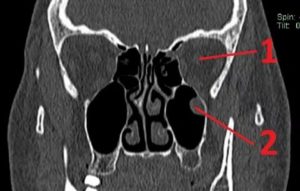

Крупные образования отоларинголог видит с помощью специального зеркала. Но он не может “на глазок” определить, откуда растет полип. Поэтому проводится инструментальная диагностика пациента:

- Магнитно-резонансная или компьютерная томография дает полную картину патологии. Врач может увидеть, где расположено основание образования, а также оценить состояние пазух. Отличить полип от кисты. Отметить присутствие гайморита и прочих синуситов, а также закупорку соустьев.

- Рентгенография более доступная аппаратная диагностика. С использованием контраста можно оценить состояние слизистой гайморовой полости, наличие полипа.